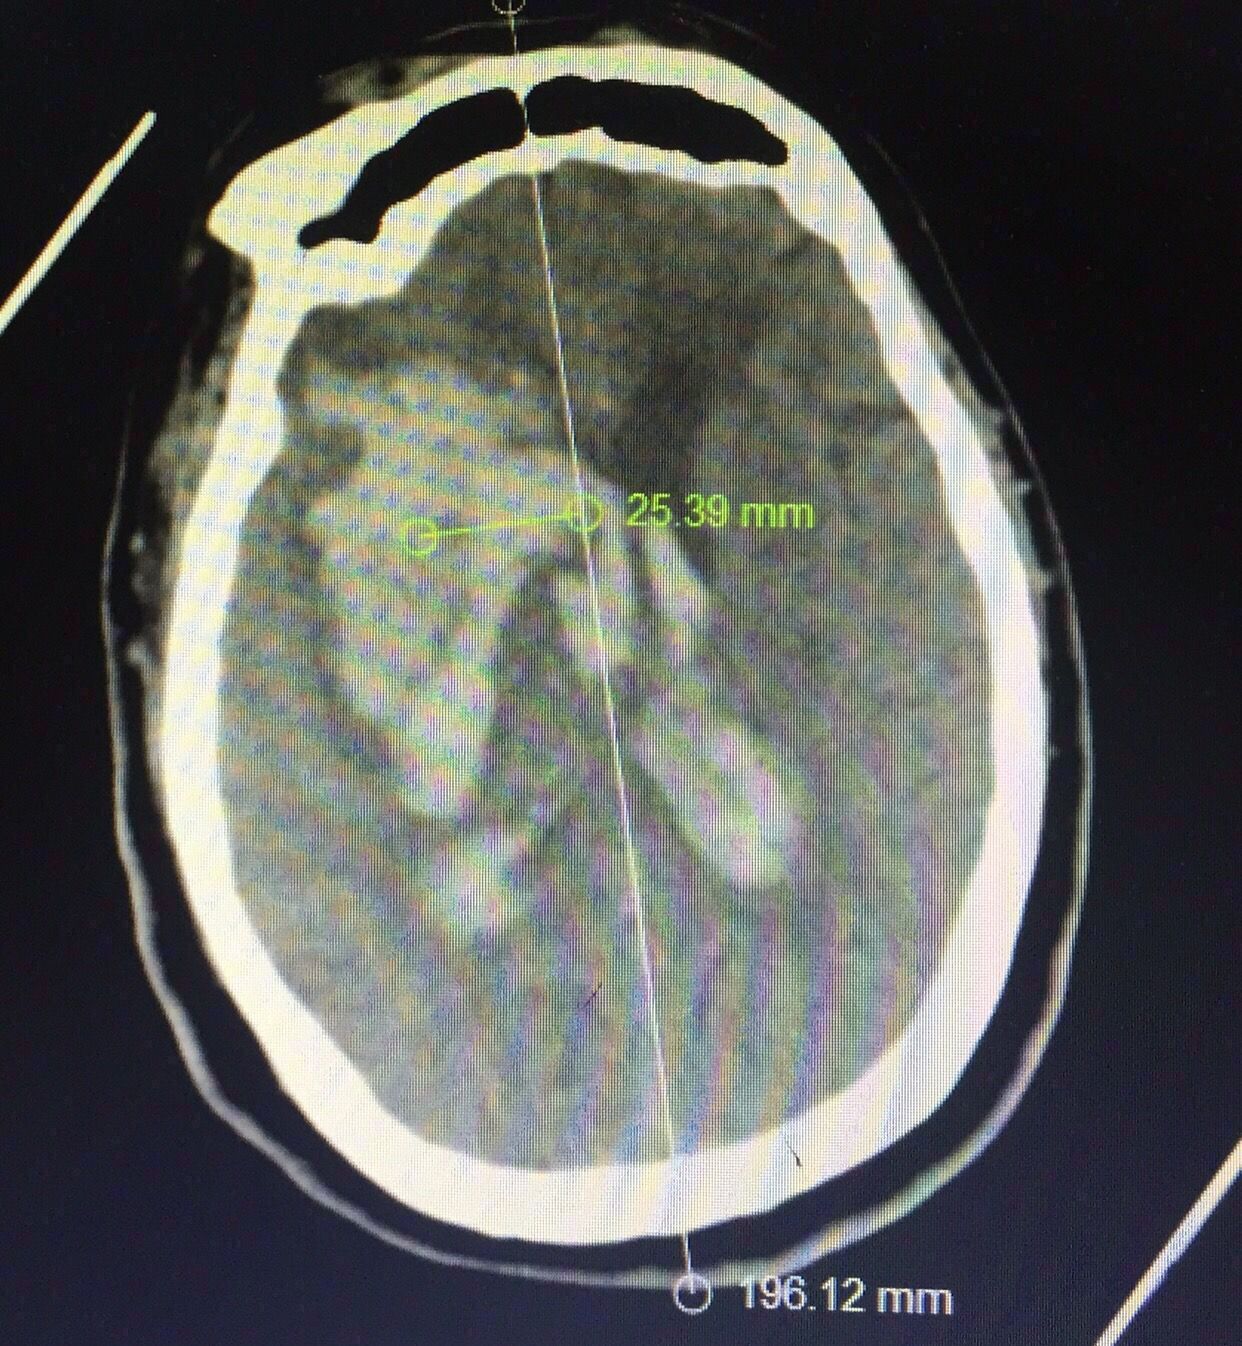

认真阅片可知,血肿最大层面就是脑室额角层面,EVD的靶点就是额角室间孔位置,我们把血肿靶点也定在这一层,右侧血肿内,右侧额角室间孔位置偏右,如图↑↑

经kocher点穿刺定位画线↑↑

中线旁开2.5㎝平行矢状线穿刺右侧血肿;偏内穿左侧脑室

中线旁开2.5㎝可以让穿刺管几乎游走在所有的血肿层面内↓↓↓↓↓↓4张照片